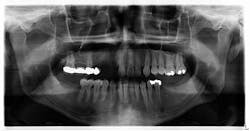

- Teeth nos. 14 and 15 both had supererupted into the 18 and 19 space (figure 2).